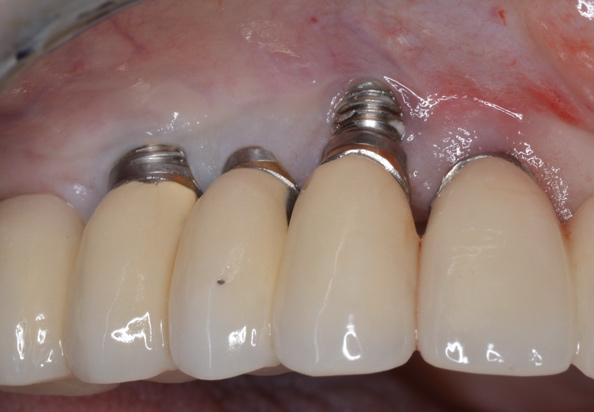

(13.) Reverse torqueing allows for a nonsurgical implant removal. No bone was sacrificed in removing these three implants.

Figure 13

(14.) One-time use reverse torque components were used to remove these implants. Portions of osseointegrated bone are still attached in the apical region.

Figure 14